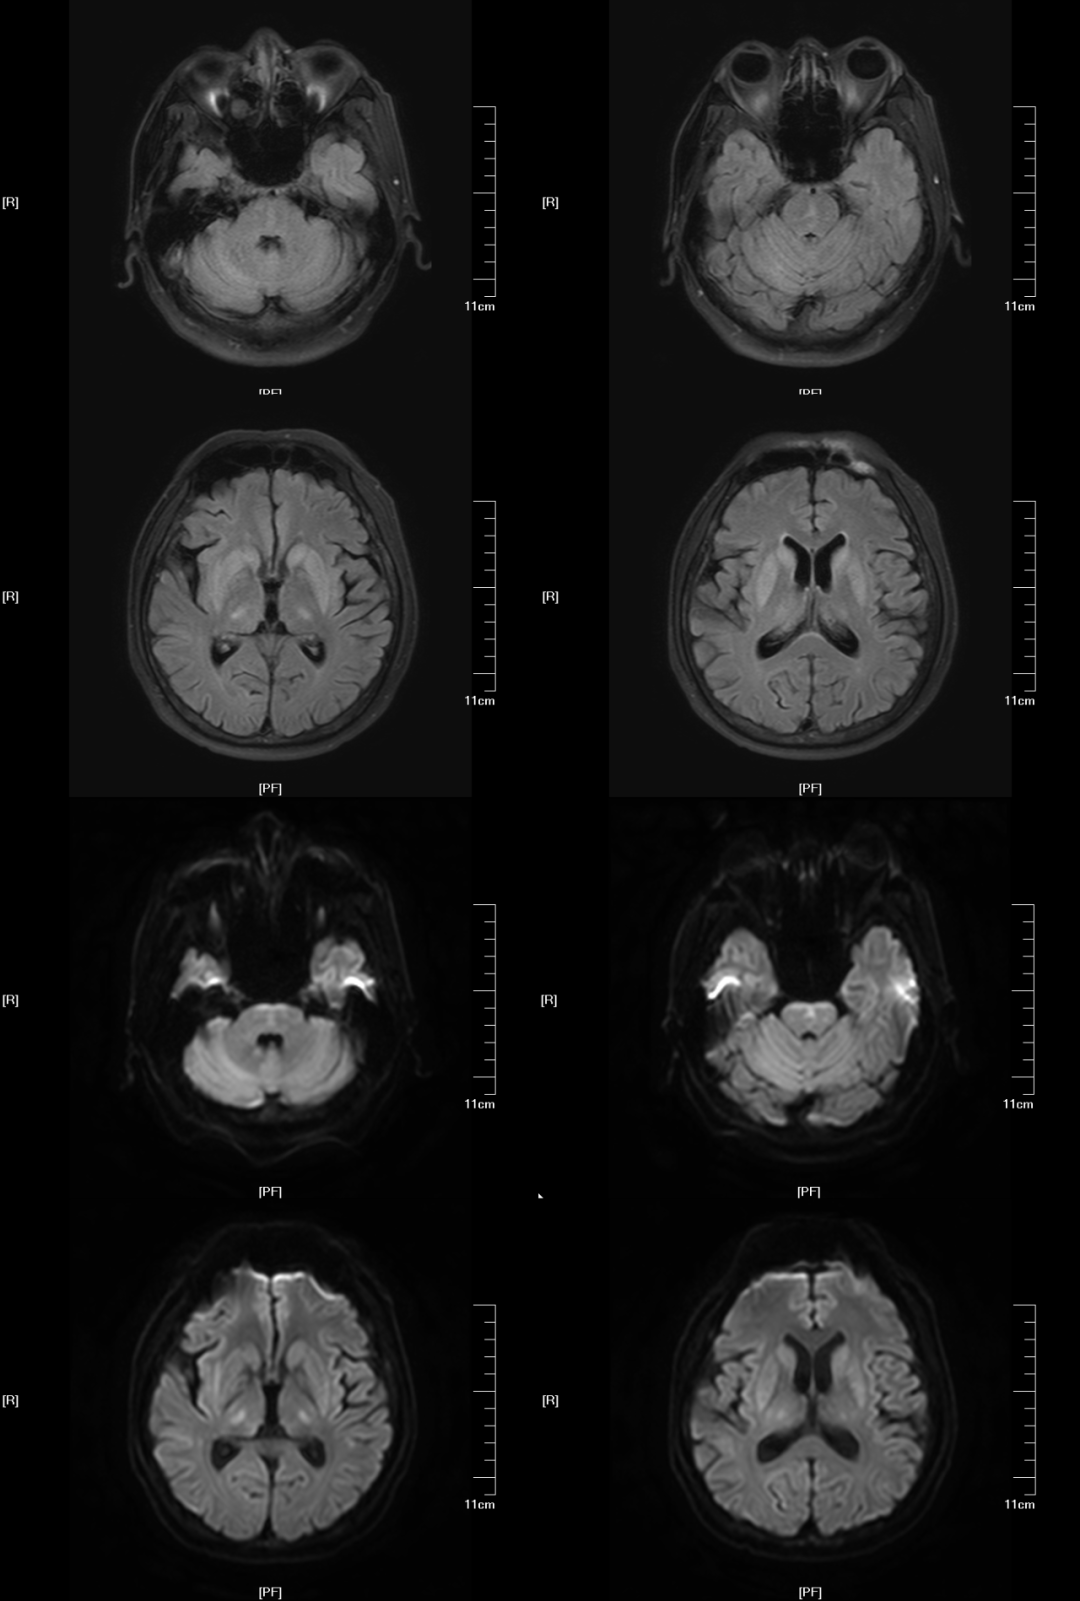

(3)EPM,病灶多对称位于基底核团或丘脑,少数病例可累及皮层,信号表现与 CPM 相似,但病灶形态不相同

对称性壳核受累,桥脑未见病灶

对称性壳核和尾状核受累,扩散受限

(4)CPM+EPM:(2) (3),MRI 与临床表现不密切相关,一般都会滞后几个星期。

桥脑“三叉戟”+基底核团+丘脑+皮层受累,扩散受限